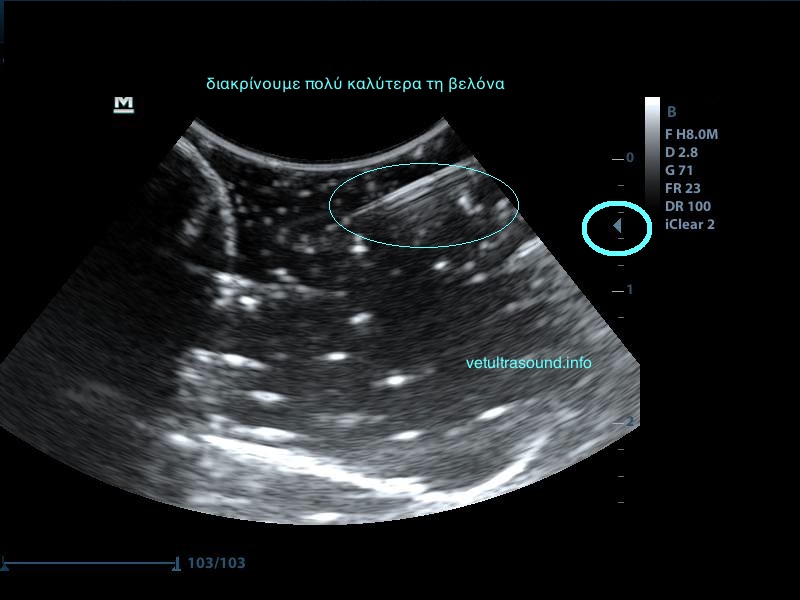

Σημαντικό ρόλο επίσης παίζει η κλίση της βελόνας σε σχέση με τον ηχοβολέα ( κεφαλή ), όσο πιο κάθετη είναι η βελόνα με τον ηχοβολέα τόσο καλύτερη εικόνα της βελόνας έχουμε, όσο αυξάνεται η κλίση τόσο μειώνεται η διακριτική μας ικανότητα.

Λόγω της κλίσης βλέπουμε μόνο την μύτη της βελόνας.

Η βελόνα εμφανίζεται κάθετα προς τον ηχοβολέα.